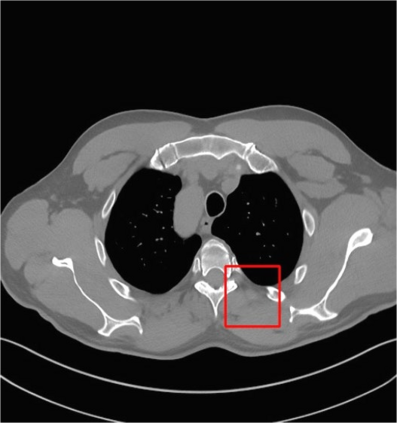

Low-Dose Computed Tomography (LDCT) technique, which reduces the radiation harm to human bodies, is now attracting increasing interest in the medical imaging field. As the image quality is degraded by low dose radiation, LDCT exams require specialized reconstruction methods or denoising algorithms. However, most of the recent effective methods overlook the inner-structure of the original projection data (sinogram) which limits their denoising ability. The inner-structure of the sinogram represents special characteristics of the data in the sinogram domain. By maintaining this structure while denoising, the noise can be obviously restrained. Therefore, we propose an LDCT denoising network namely Sinogram Inner-Structure Transformer (SIST) to reduce the noise by utilizing the inner-structure in the sinogram domain. Specifically, we study the CT imaging mechanism and statistical characteristics of sinogram to design the sinogram inner-structure loss including the global and local inner-structure for restoring high-quality CT images. Besides, we propose a sinogram transformer module to better extract sinogram features. The transformer architecture using a self-attention mechanism can exploit interrelations between projections of different view angles, which achieves an outstanding performance in sinogram denoising. Furthermore, in order to improve the performance in the image domain, we propose the image reconstruction module to complementarily denoise both in the sinogram and image domain.